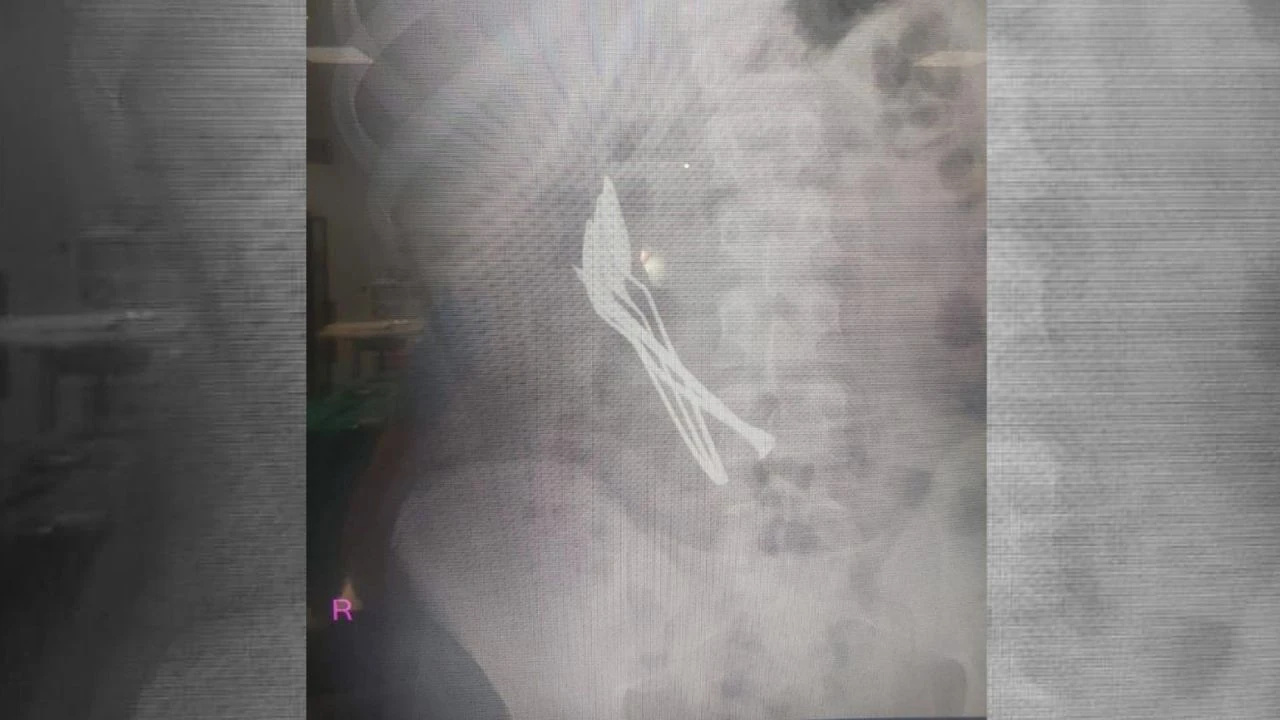

Kayseri'de mide rahatsızlığı çeken 15 yaşındaki çocuk Kayseri Şehir Hastanesine gitti. Yapılan ilk müdahalede röntgeni çekilen çocuğun midesinde 4 adet kaşık ve 1 adet çivi olduğu tespit edildi.

Çocuk Cerrahisi ve Ürolojisi Anabilim Dalı Başkanı Doç. Dr. Mustafa Erman Dörterler tarafından ameliyatı yapılan çocuğun midesinden 4 adet metal çay kaşığı ve çivi çıkarıldı.